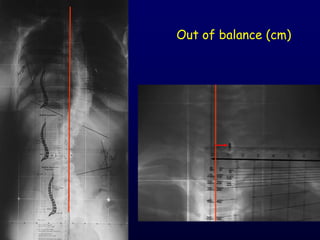

X-Rays

LATERAL

Ηάμρε ώμςκ 90°

Ιεηνηθό ζθάιμα + - 5º

Cobb – Lippman

1948

Out of balance (cm)

AP Απόζηαζε 2 m Films:36 x 91 cm 36 x 43 cm Σ1 - S1 Ημνμόξ: Χςνίξ ζηνμθή Δηόνζςζε ακηζμζθειίαξ X-Rays LATERAL Ηάμρε ώμςκ 90°